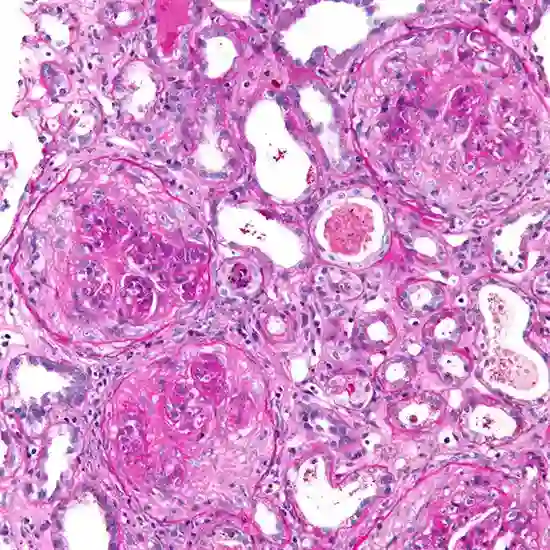

• Kidney biopsy: A test in which tissue samples are removed and checked under a microscope to check good pasture syndrome antibodies.it also helps in identifying the extent of tissue damage.